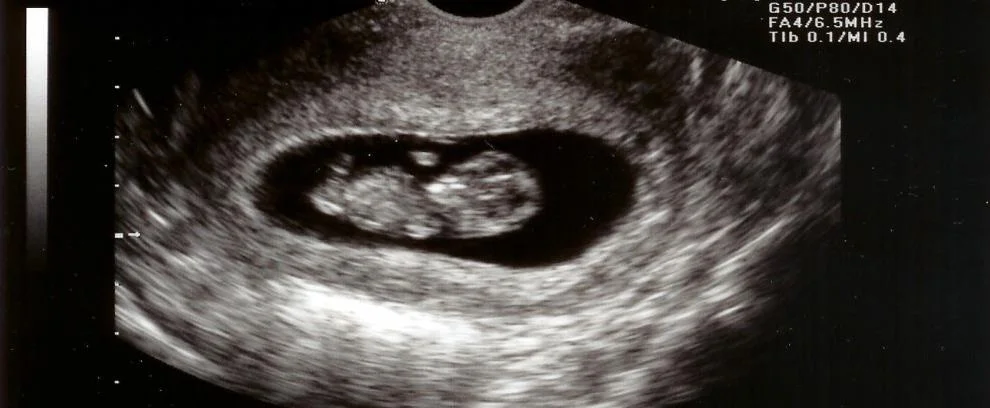

- US: absent fetal heart pulsations.

| Missed miscarriage | IUP No FH | A symptomatic often diagnosed at booking UUS | Expectant medical or surgical |